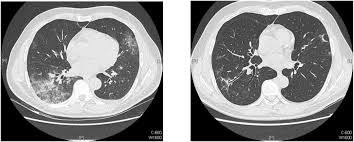

Frontiers Fatal Pneumonia Associated With A Novel Genotype Of Human Coronavirus Oc43 Microbiology

Asymptomatic Hypoxia In Covid 19 Is Associated With Poor Outcome International Journal Of Infectious Diseases

Jcm Free Full Text Low Dose Chest Ct And Lung Ultrasound For The Diagnosis And Management Of Covid 19 Html